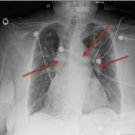

A 60-year-old woman presented with a 4-day history of right-sided anginal chest pain, palpitations, vaginal pain, and dysuria.